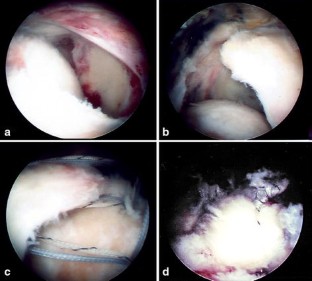

Fig. 8